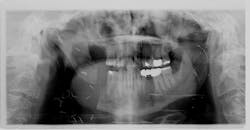

In March 2013, a then-70-year-old male presented to our office for a new-patient exam with a specific request to have an “irritated” tooth in the lower right evaluated. The patient disclosed a previous history of skin cancer in 2007, with a lesion removed from his cheek and subsequent loss of a salivary gland on the right side. A large visible scar over the right masseter area was present, and the patient explained that the surgery had left him with limited ability to open his mouth and care for the teeth on that side. Tooth no. 31 showed significant bone loss on the distal aspect but was otherwise solid (figure 1).